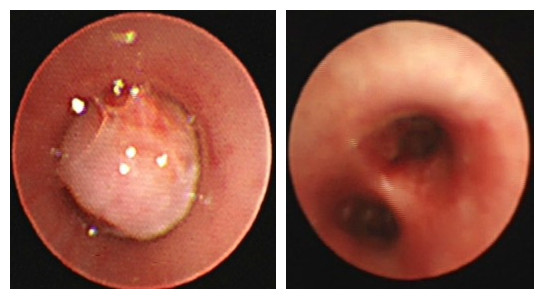

被被肿瘤完全遮挡的气道和术后畅通的气道

钟礼立、黄寒主任带领的儿童呼吸介入团队仔细对小涵进行体查,发现其左肺基本听不到呼吸音,意味着他的左肺通气受到了严重影响,为明确诊断,医生为小涵进行了支气管镜检查,从镜下发现小涵左主支气管有一肿物已完全阻挡气道,直接影响通气功能,更糟糕的是,肿物周围血供丰富,触碰易出血,不能贸然取组织进行活检,否则可能会导致大出血。